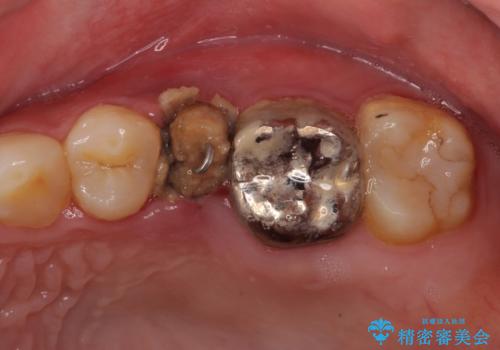

- 他院で大きな虫歯の歯を引っ張り出す治療中、あまりにも異臭がするとのことで来院された患者様です。

診査したところ、虫歯が広範囲で、粗造になった歯の表面に汚れがこびりついていました。また、歯根の半分以上の深さにまで亀裂が生じており、保存は不可能と診断しました。